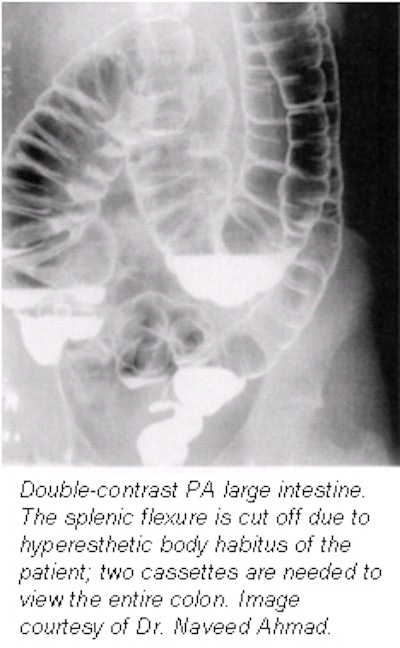

Patient positioning, imaging techniques for routine single-contrast barium enema

The basic principle for performing an accurate single-contrast barium enema is radiography of the colon so that all segments of the colon are clearly seen without overlapping loops. It is also necessary that each segment of colon be seen at fluoroscopy and on at least two films so that any suspected lesion can be verified.

This is accomplished by a combination of fluoroscopy and compression spot films of the entire colon, as well as bucky films of the entire colon. Compression spot filming is employed to thin out the barium column so that a small lesion, such as a polyp, can be easily seen. However, the rectum and the pelvic loops of the sigmoid colon are not amenable to compression. A through examination incorporates the following procedures and film sequences.

Overhead films

All overhead films must be taken at 110 kVp; suggested films which should be obtained are the following:

- A posteroanterior (PA) axial projection should include the rectosigmoid area (14 x 17-inch, or 36 x 40-cm IR). The PA projection with the patient in prone projection is preferred over an AP in supine as it results in a more uniform radiographic density of the entire abdomen. The entire colon, including the rectum, should be clearly seen.

- A PA oblique projection in the left anterior oblique (LAO) position (14 x 17-inch, or 36 x 40-cm IR) should include both flexures.

- A PA oblique projection in the right anterior oblique (RAO) position (14 x 17-inch, or 36 x 40 cm-IR) should include both flexures.

- A post-evacuation film. After the radiologist reviews the overhead films, send the patient to the restroom to evacuate as much barium as possible, and obtain an AP abdomen (14 x 17-inch, or 36 x 40-cm IR) post-evacuation film on a horizontal table using 90 kVp.